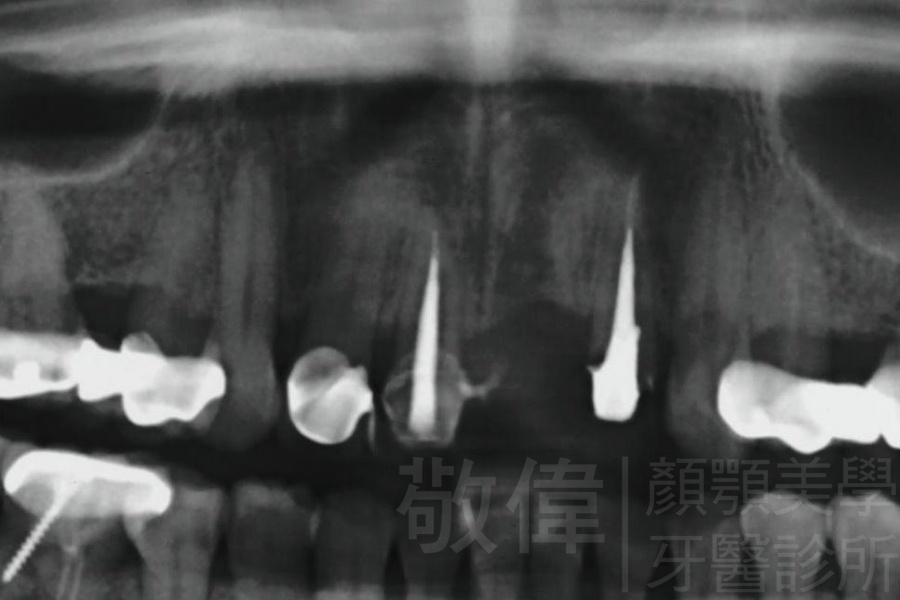

治療前-缺牙區X光   治療後-大臼齒X光